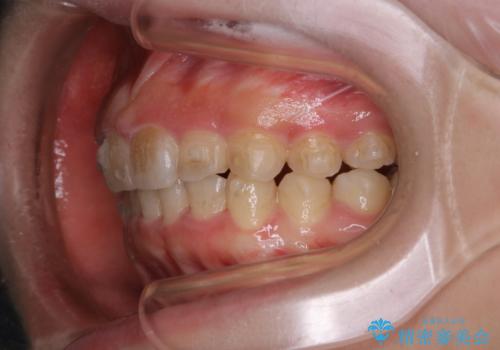

インビザライン中にステインの除去

- インビザラインでのマウスピース矯正中の方で、歯の表面のステインをきれいに取りたいとのことでした。PMTC60分コースを行いました。

PMTC(保険外治療)は、毎日の歯磨きで落としきれない汚れや、コーヒ、紅茶・タバコのヤニなどの着色も除去します。目には見えない歯と歯の間・歯肉の境目・インビザライン中はアタッチメント周囲などに残っているプラーク(歯垢)もしっかり取り除きます。PMTCでは専門的な機械や材料を使用して、徹底的に汚れを除去するため、虫歯・歯周病・口臭予防などにつながります。